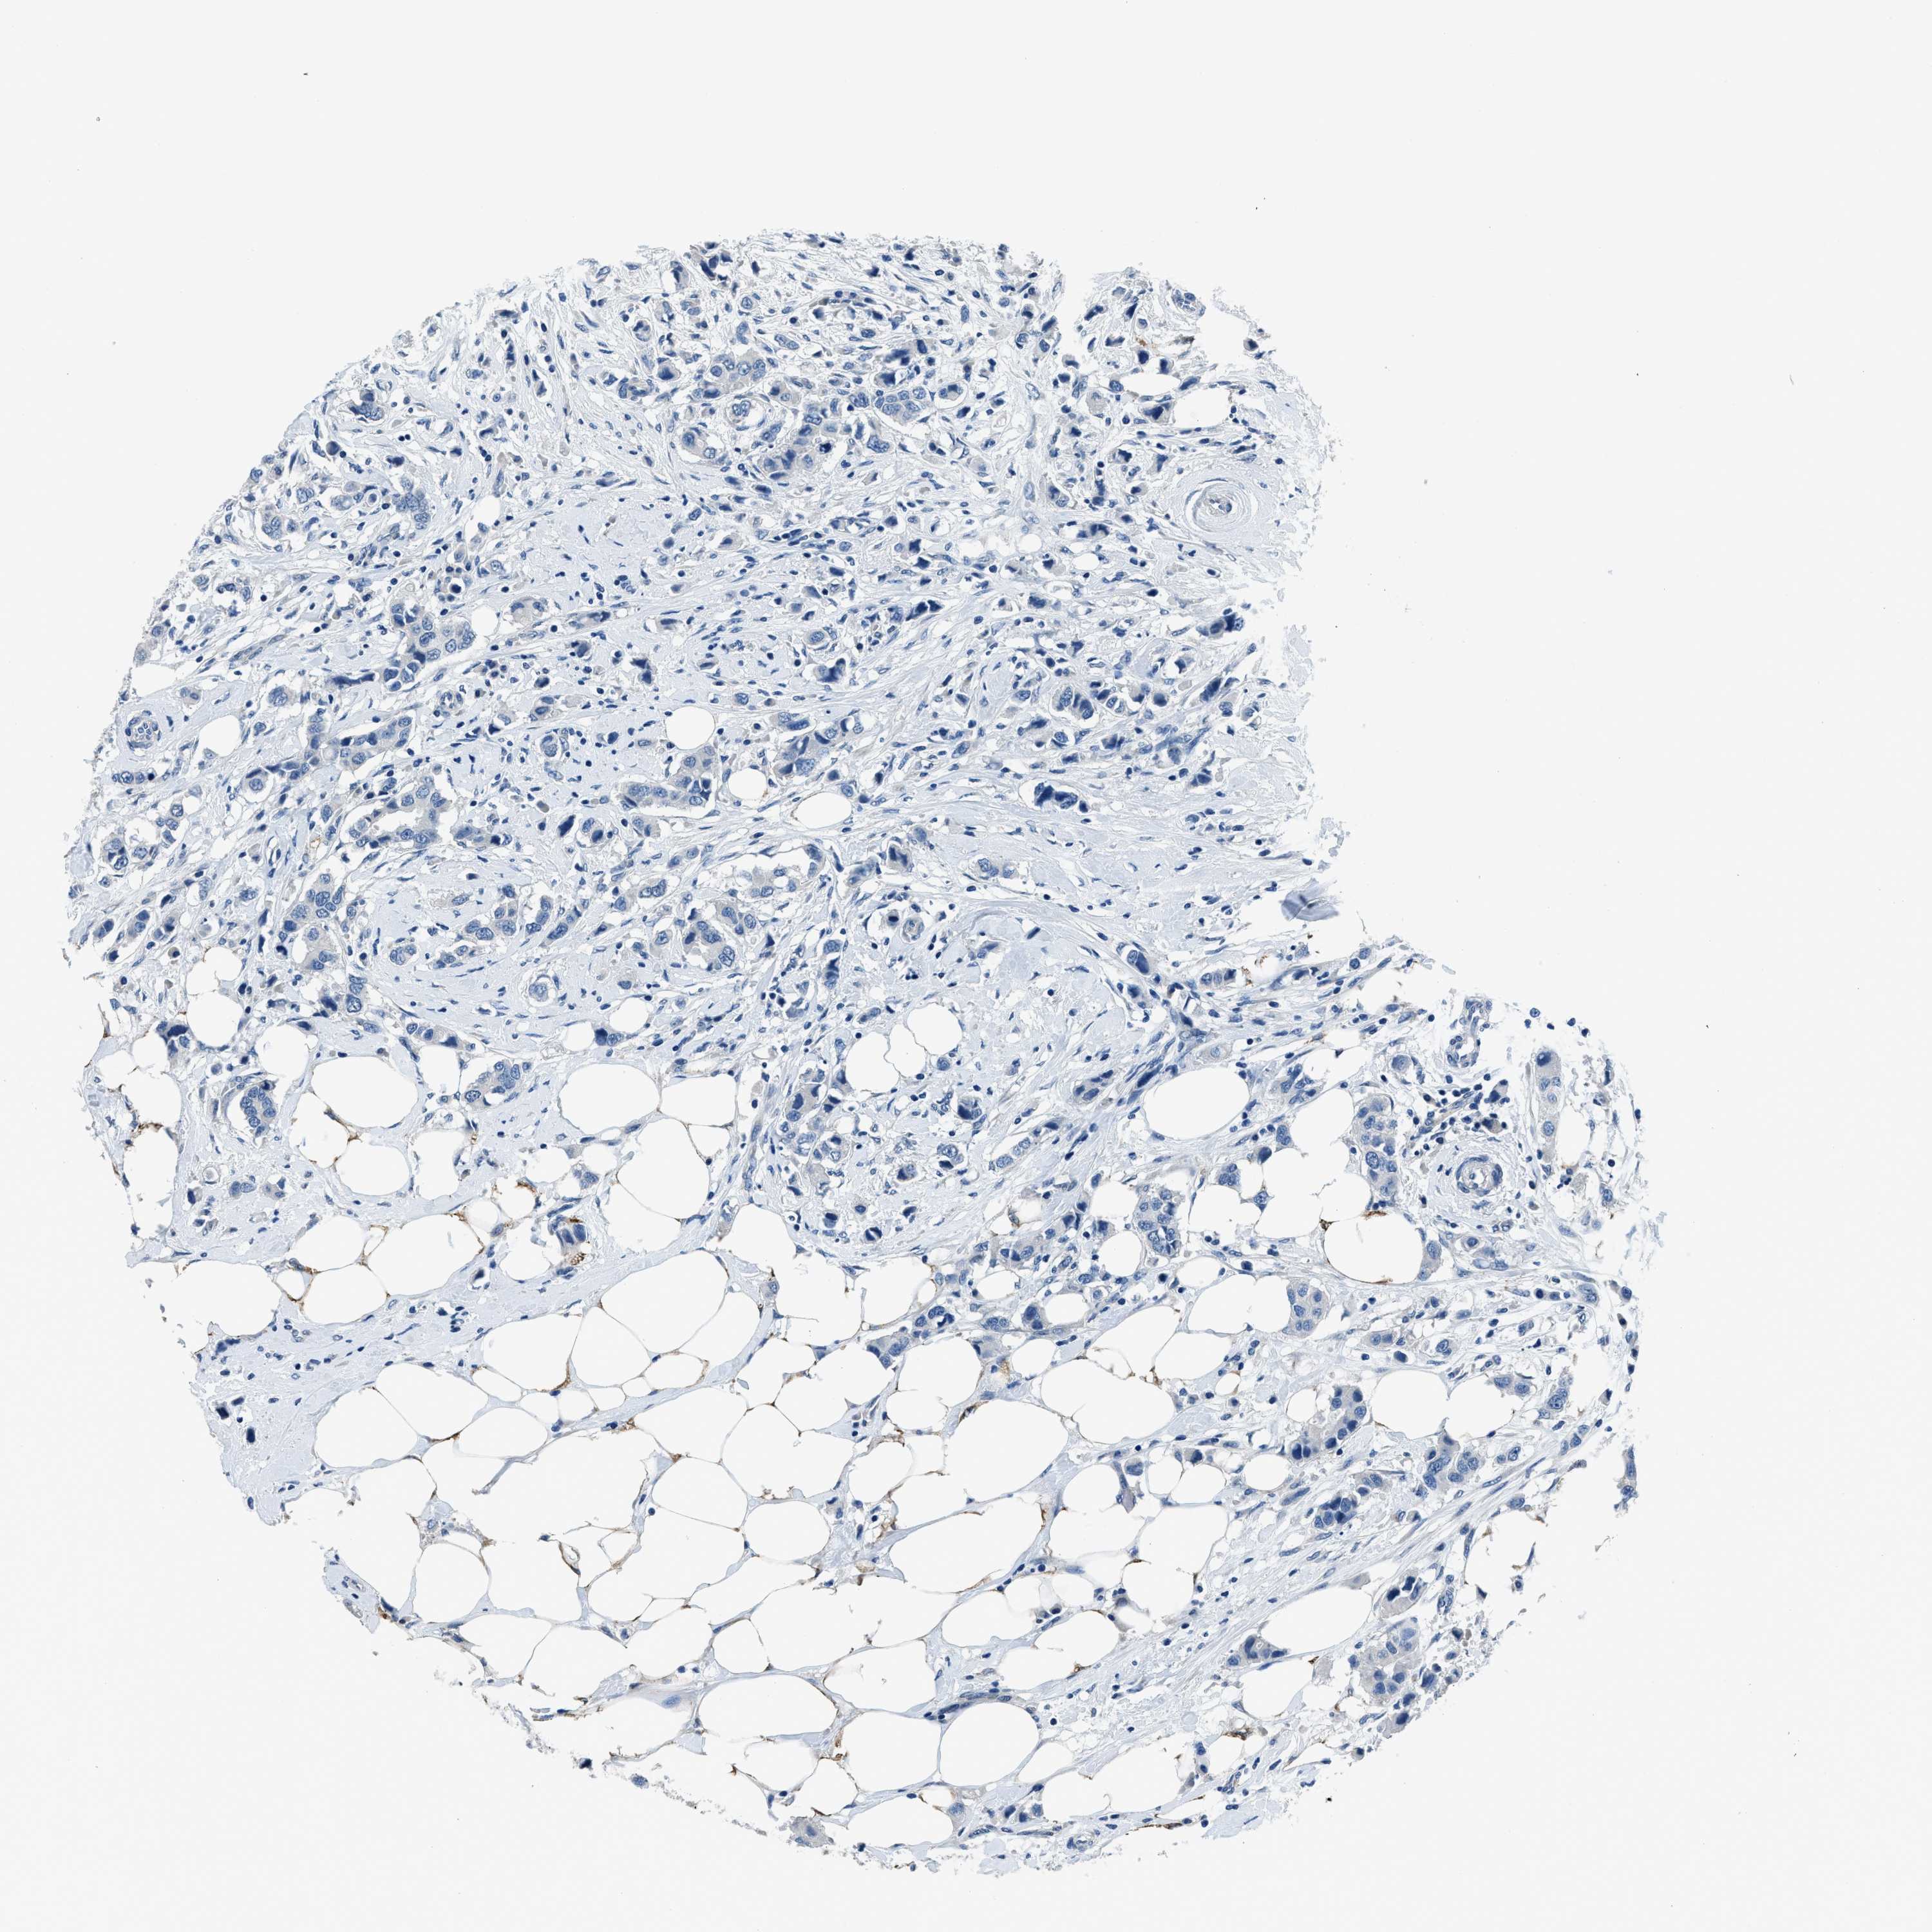

CANCER BREAST CANCER Show tissue menu

BRCA TCGA BRCA VALIDATION PROTEIN EXPRESSION